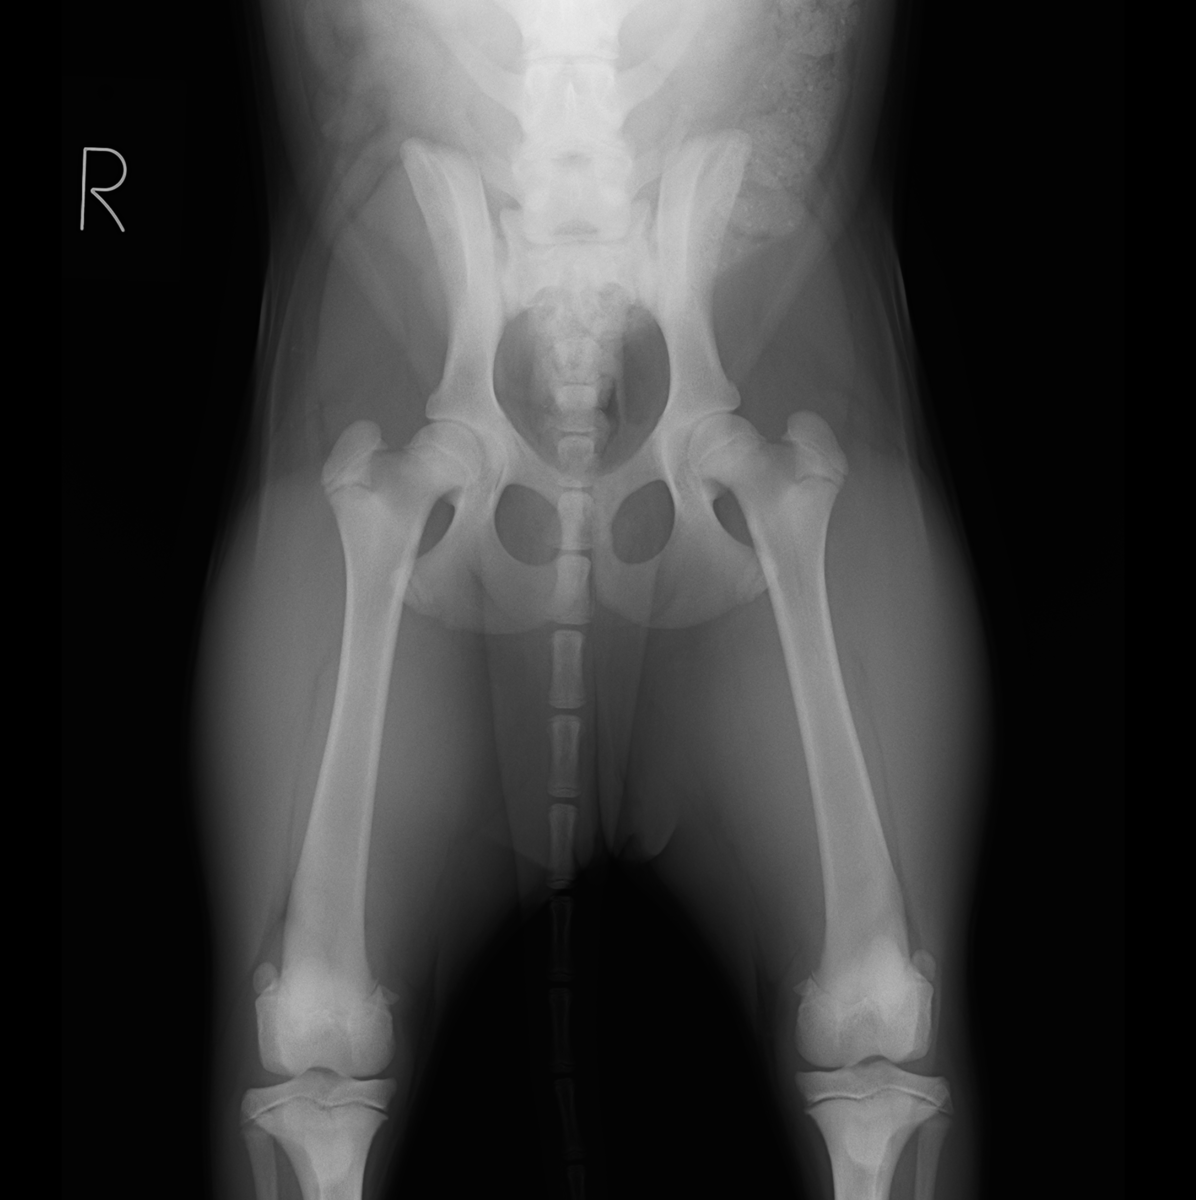

病院犬(生後約4ヶ月)の股関節を、PennHIP(ペンヒップ)という特殊器具を用いたレントゲン撮影を先日実施しました。

撮影をした理由としては少し腰を振って歩いていたり、足を投げ出す様に座っていていて、股関節形成不全が疑われたからです。

下にあるのが実際に撮影したレントゲンになります。

下の図にあるようなディストラクター(下の写真)とよばれる特殊な器具を用いて、三つの体位で股関節を撮影し、股関節の緩みをレントゲン画像上で可視化し、その緩みの数値を測定します。